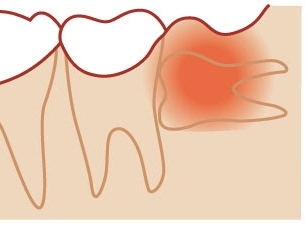

「親知らず」ってどういうときに抜くの |

|

![]() 親知らずの抜歯などの口腔外科

親知らずの抜歯などの口腔外科